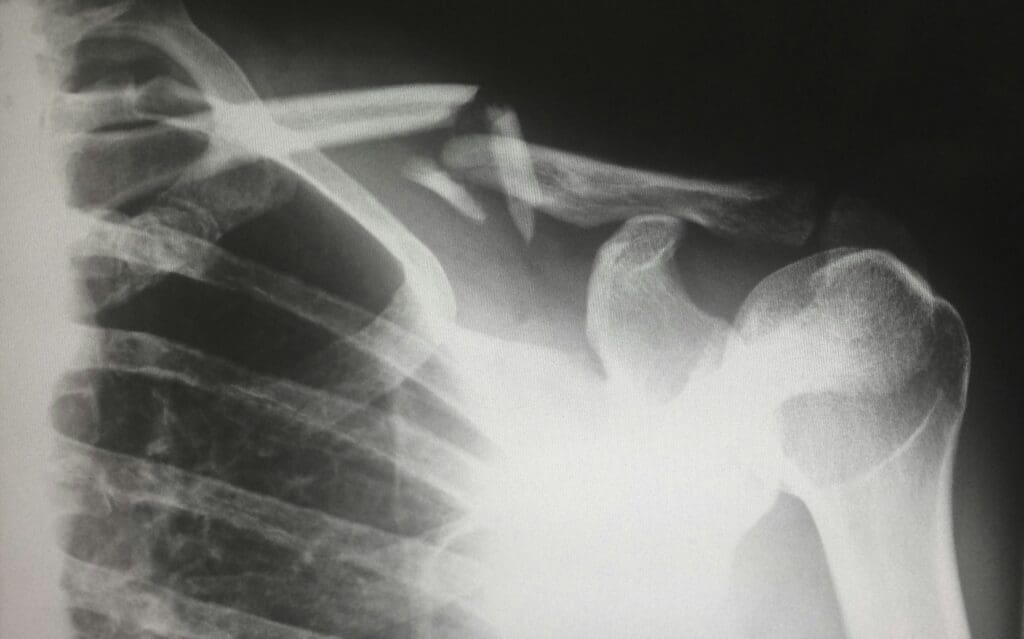

Fractures represent a common occurrence in athletic school sports, often resulting from sudden impact, falls, or repetitive stress on bones. They can be categorized into three primary types: simple (or closed) fractures, compound (or open) fractures, and stress fractures. Each type exhibits distinctive characteristics and symptoms that are crucial for identification and management.

A simple fracture occurs when a bone breaks but does not penetrate the skin. Symptoms may include localized pain, swelling, bruising, and the inability to use the affected limb. Conversely, a compound fracture involves a break in the bone that protrudes through the skin, posing a higher risk of infection. This type is typically accompanied by severe pain, visible bone fragments, swelling, and deformity within the affected area.

Recognizing when a fracture has occurred is vital for appropriate intervention. Key indicators include sudden, intense pain, swelling, and any observable deformity. If an athlete suspects a fracture, it is imperative to seek medical attention without delay. Failure to address a fracture can lead to improper healing and potential long-term consequences, including chronic pain or mobility issues. Prompt evaluation and treatment by a healthcare professional can ensure the best outcomes. Awareness of the signs and types of fractures can greatly aid in managing injuries sustained during athletic school sports, ultimately supporting better recovery and safety for young athletes.